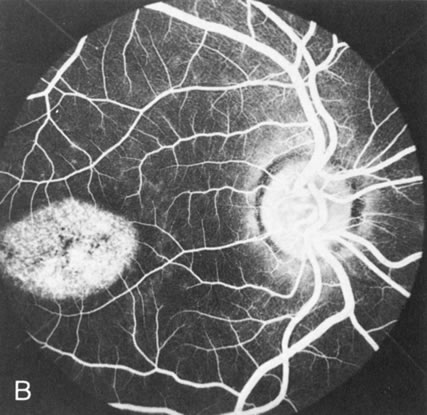

In Stargardt's disease, thes most common hereditary macular dystrophy, FA has a variety of functions. In the mildest fundus presentation, with visual symptoms and visual function out of proportion to the observed maculopathy, FA can confirm or even make the diagnosis and can avoid a mistaken diagnosis of malingering, hysteria, or central nervous system disease (Fig. 9A and B). When a maculopathy is present without surrounding parafoval flecks, FA may show patchy areas of transmission hyperfluorescence in the posterior pole, indicating a more diffuse involvement (Fig. 9C and D).

Fig. 9. Stargardt's disease–fundus flavimaculatus. The mild maculopathy (without parafoveal flecks) (A) is confirmed by the angiogram (B). The relative absence of the underlying choroidal flush, resulting in an easier visualization of the overlying retinal capillary circulation, has been referred to as the “silent” or “dark” choroid, and is considered a common finding in this disease. The diagnosis is confirmed in an individual with a pigmentary maculopathy without flecks (C). Here the angiogram demonstrates widespread transmission hyperfluorescence and a “silent” or “dark” peripapillary area (D). When the posterior pole shows multiple yellowish-white flecks (E), the angiographic findings do not necessarily correspond to the flecks (F). It should also be noted that despite the widespread abnormalities, the background choroidal fluorescence is normal.

In a large majority of patients (86% in one study),20 there is an absence or decrease in the background choroidal fluorescence (which is referred to as the “silent” or “dark” choroid) (see Fig. 9B). This warrants special attention because it occurs so frequently, is rarely found in other retinal disorders,21 and may be related to histopathology that shows an increase in lipofuscin in the RPE.22